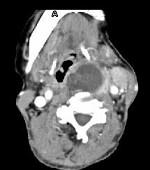

问题 女,64岁,发现双甲状腺肿大1月余,CT如图所示,最可能诊断为()

选项 A.结节性甲状腺肿 B.甲状腺腺瘤 C.甲状腺癌并淋巴结转移 D.甲状腺转移瘤 E.甲状腺结核

答案 C